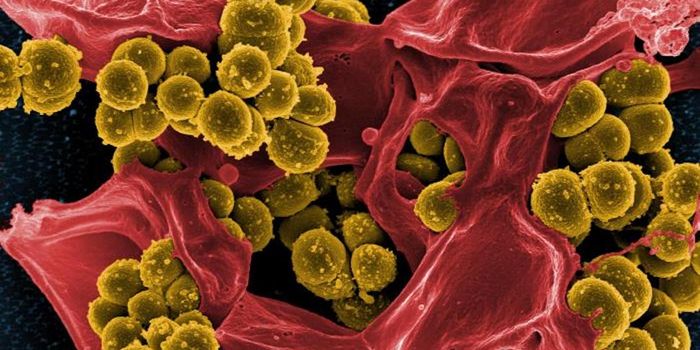

SEP 17, 2021Cell & Molecular BiologyMRSA (methicillin-resistant Staphylococcus aureus) is a well known superbug, a pathogenic microbe that can cause serious ...